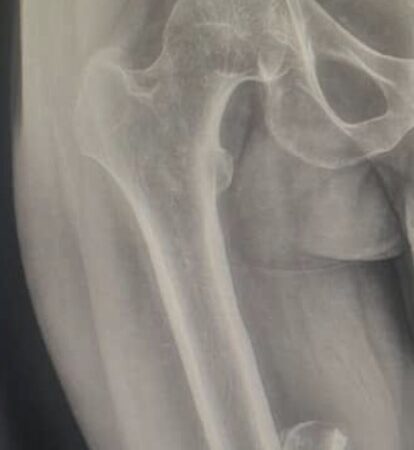

“I sustained fractures to both my right and left femurs during a serious accident two years ago. By God’s grace, my left femur has fully healed. However, my right femur did not heal properly. Recent X-ray examinations revealed a malunion, meaning the bone joined incorrectly, which has continued to limit my mobility and cause ongoing pain.